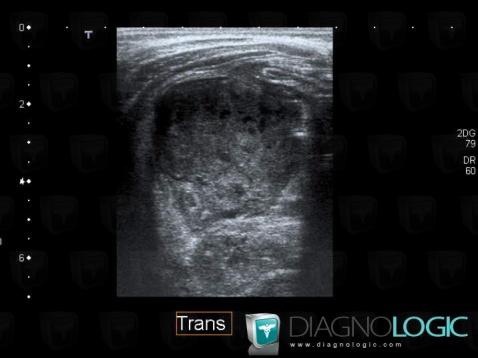

Abscess, Caecum / Appendix, US

Here is the specific information in the key image above:

- Diagnosis Abscess, Location(s) Caecum / Appendix, with gamuts Cecal / lleocecal valve lesion, Pericecal fat infitration, Appendiceal lesion